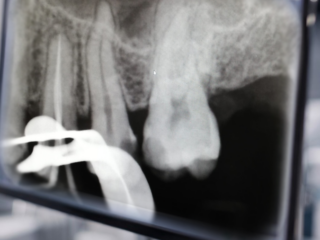

Endodontie

Traitement des Racines

Sauver une dent qui ne peut plus être soignée simplement.

L’endodontie intervient lorsque la pulpe de la dent (le nerf) est touchée, soit par une carie profonde, soit par un choc. Pour éviter l’extraction, nous désinfectons l’intérieur des racines et les scellons de manière hermétique. C’est l’étape ultime qui permet de conserver votre dent naturelle sur l’arcade et d’éviter son remplacement par un implant ou un bridge.